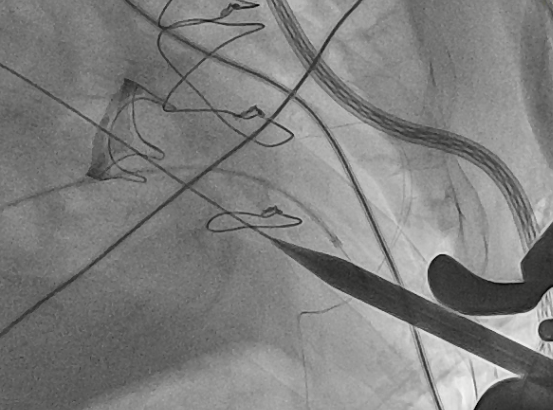

交换加硬导丝

扩张鞘预扩心尖穿刺点

输送器进入左室至生物瓣下方